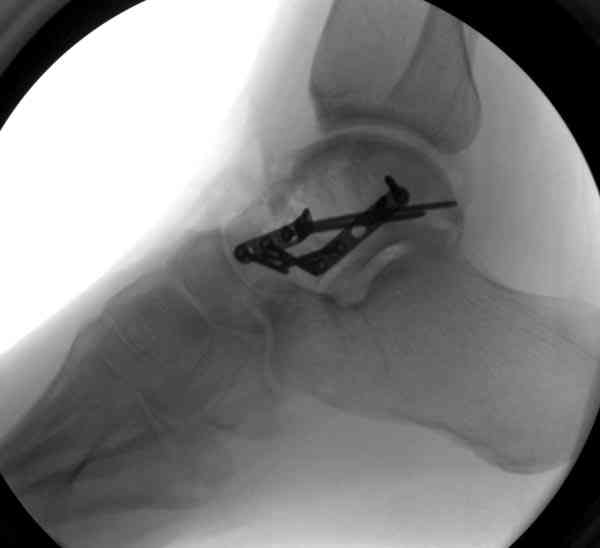

Случай с множественным оскольчатым переломом тарана оперированный из двойного доступа.

Через 2 мес.:

Через 8 мес.:

Через 14 мес.:

И второй случай из недавней ташкентской практики, (извините за качество ренгенограммы и только в одной проекции) случай падения с высоты (кстати моего друга - известного киноактера) - открытый

смещенный перелом тарана, с переломом переднего края дистального эпиметафиза большеберцовой кости.

При поступлении в приемной сделана первичная обработка с ушиванием открытой латеральной раны и вытяжением за пятку.

Из-за отсутствия времени пришлось оперировать на второе утро, из материала, что имеем на месте, фиксирован двумя шурупами, а третий-это контур сломанного жойстика в 4 мм. На дистальный медиальный конец тибиа antiglide 3.5 мм пластина. Через пару дней выписан и несмотря на предупреждение, самостоятельно начал нагрузку в 4 недели, время не ждет, снимается в боевике в Росийской Федерации.